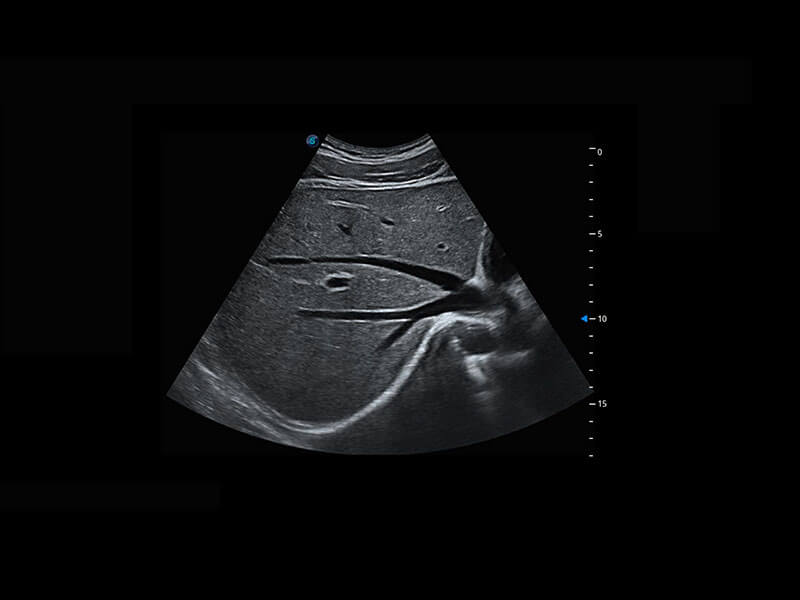

生殖健康

P60优异的图像质量搭载专科探头,在妇科基础疾病的诊断、卵泡生长的监测、输卵管通畅情况的判别等方面为您提供生殖应用方案。

• 腔内妇科-宫腔分离

• 腔内妇科-卵巢

• 腔内三维-宫内节育器

• 腔内三维-光影成像